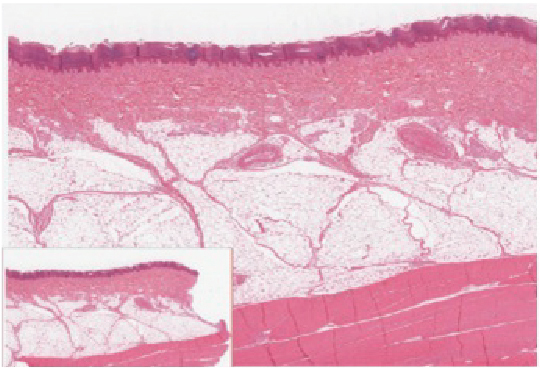

The outer layer of cells in this micrograph is the thinnest layer and stained deep purple due to full keratinization of dead cells. The next layer occupies one quarter of the micrograph, is lightly stained, and is a dense collection of cells. The third layer from the top is mostly white, with lightly stained, loosely-packed strands radiating in random directions. The bottom-most layer is densely-packed, with thick bands of highly organized muscle tissue that are darkly stained.

Figure 5.1.3 – Epidermis: The epidermis is epithelium composed of multiple layers of cells. The basal layer consists of cuboidal cells, whereas the outer layers are squamous, keratinized cells, so the whole epithelium is often described as being keratinized stratified squamous epithelium. LM × 40. (Micrograph provided by the Regents of University of Michigan Medical School © 2012)